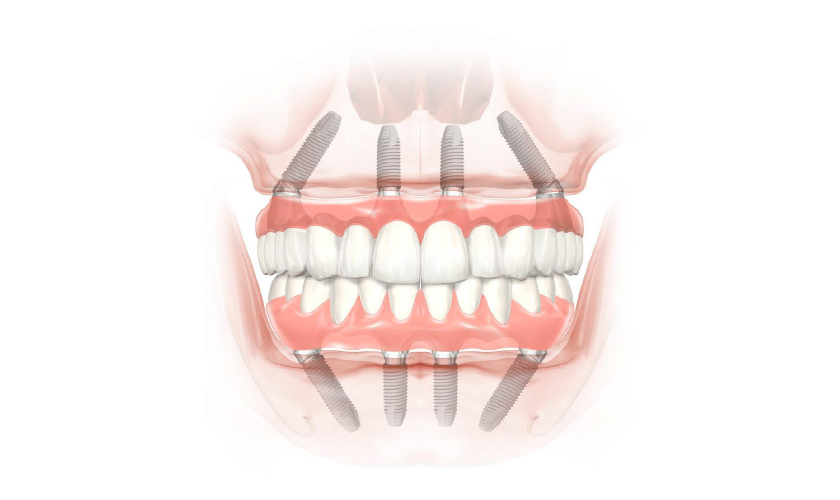

Với kỹ thuật Implant All on 4, Bác sĩ chỉ sử dụng 4 Implant trên 1 hàm, bao gồm 2 Implant giữa được cấy thẳng góc và 2 Implant phía bên được cấy nghiêng với góc nghiêng tối đa 45 độ, cùng với sự hỗ trợ của Multi-unit Abutment nâng đỡ, giúp cho phục hình trên 4 Implant đạt được 12 răng/hàm.

Kỹ thuật này cấy ghép 4 Implant vào xương hàm, trong đó 2 trụ Implant giữa được cấy thẳng và 2 trụ Implant bên được cấy nghiêng với góc nghiêng tối đa lên tới 45 độ. Quá trình cắm trụ Implant sẽ được chia làm 2 lần, mỗi lần cắm 2 trụ Implant nhằm đảm bảo hiệu quả và an toàn cho khách hàng.

Kỹ thuật cấy ghép Implant All on 4